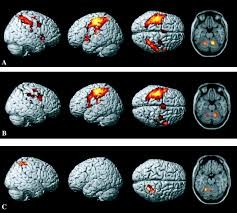

The interior of the building is formal, clean, cold and sterile like any medical lab. All the walls, tables, chairs and glasses are official as if you are aware of what kind of institution this place is. Seriousness is ingrained in things. As the research began, I took my place in front of a large window in a cockpit-like control cabin amongst crammed rows, digital devices, three giant computers, and a group of researchers in white. The $ 4 million machine (fMRI - Functional Magnetic Resonance Imaging) covering the room we looked at through this large glass and resembling a giant donut sculpture was about to begin the show. FMRI, the most advanced technique of the day, measures the magnetic properties of hemoglobin in red blood cells that carry oxygen to the whole body. In other words, thanks to this machine, you can see to which part of your body the most oxygen is being transported. Combined with the knowledge that the most working region needs the most oxygen and a measurement precision of up to one millimeter, your brain is an invention that can instantly measure which areas are working and open a legendary door to human intellectual processes such as decision-making.

Five weeks later, the leader of the team, Dr. Calvert put the results before me. I was stunned to say the least. Findings Dr. He even stunned Calvert: the warning signs on the sides, front and back of the cigarette packs had no effect on calming the smoker's cravings. Zero impact. In other words, so all these scary pictures, government regulations, billions of dollars spent by 123 countries on anti-smoking campaigns, were all wasted in the final analysis. I didn't say anything but "Are you sure?"

Yet this is Dr. It wasn't even half as surprising as what Calvert discovered when he analyzed the results more thoroughly. Whether it is American warnings in the form of a gentle reminder, direct British warnings with black boxes, or images of the mouth, lungs, and feet in a terrifying wound - in fact, the nucleus accumbens (accumbens nucleus) known as the 1 desire point in smokers' brains. This zone is the part of specialized neurons that start to radiate when the body desires something - be it alcohol, drugs, tobacco, sex, or gambling. Once the acumben nucleus is stimulated, it needs a higher dose each time to be satisfied.

In short, the results of the fMRI device showed that the warnings about smoking and its results on the packages were not effective in deterring smokers from smoking, and even encouraged the smoker by saying "burn a cigarette", so to speak, by stimulating my core.

Most of the smokers we asked if the reminders were helpful had the answer "yes" pasted right away; But perhaps it was because of the "right" answer, or the fact that the researcher thought this was what he wanted to hear, or the guilt of knowing that smoking was bad for health. However, Dr. Calvert's later analysis revealed that the cause was not related to the sense of guilt for the harm smokers cause to their bodies by smoking. The reason for the guilt feelings of smokers was that the warning letters stimulated the desire regions in their brains. Well, their conscious mind couldn't make this distinction. While Marlene was filling out the questionnaire, she had not yet entered the machine. But his brain - the firmest place that left no nonsense - was stubbornly wrestling with himself. Just like each of us does every day with our brains.